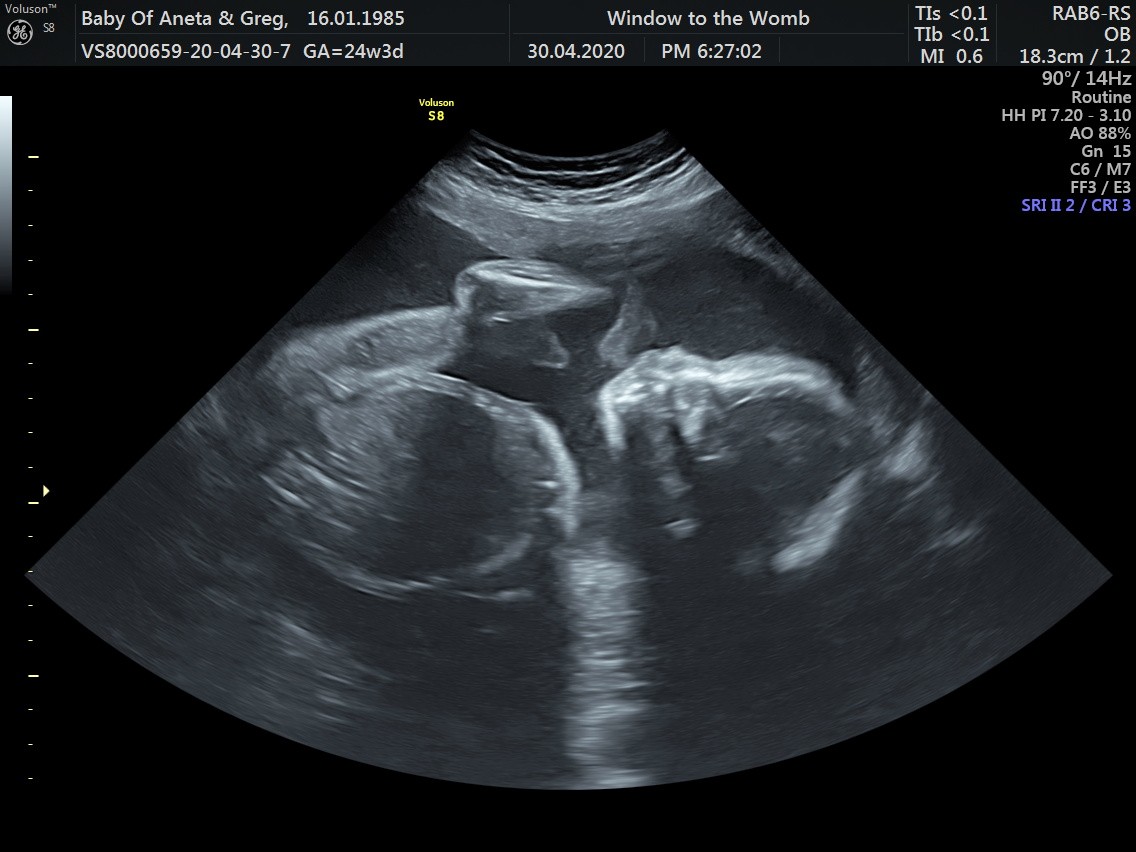

Wszystko z bejbikiem ok, wazy już 700g rozwija się według tego co powinien czyli dalej ma 24 tygodnie.

Łożysko poszło do góry, ale mięśniak rośnie. W miesiąc powiększył się o 3cm wiec ma już 7cm średnicy i całkowicie zasłania szyjkę. Ten ból który czuje to od ucisku przez mięśniaka.